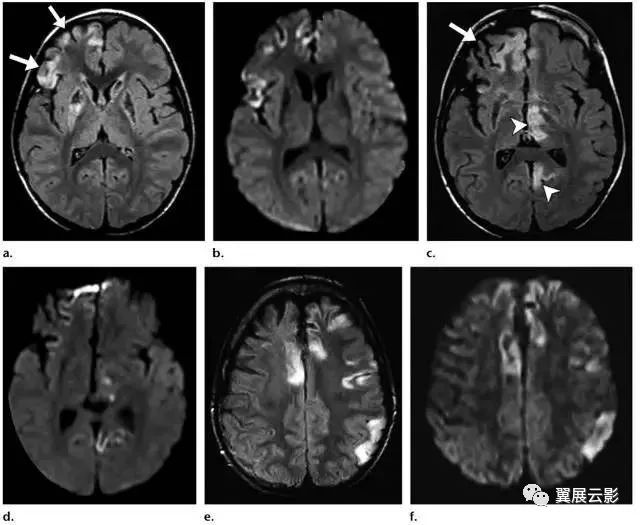

影像处理技术的不断升级,使得医学影像在识别和分析疾病方面的表现愈发突出。UTJ55.656影像处理版作为一种先进的医学影像处理软件,通过高效的算法,可以实现对图像的实时处理与分析,为医生提供更详细的病灶信息。这些技术的运用,能够显著提升诊断的准确性及效率。

- 多模态集成:该系统可以整合多种影像来源,如CT、MRI和X光等,实现综合性分析。

- 智能识别功能:通过深度学习技术,该系统能够自动识别和标记影像中的病变区域,大幅度减少了人工干预的需求。

某大型医院在开展肿瘤早期筛查时,采用了UTJ55.656影像处理版进行影像资料的分析。在结合多种影像技术的基础上,医生能够早期发现患者体内微小的病变,显著提高了早期诊断的成功率。经过进一步的分析与验证,患者最终接受了及时的治疗,治愈率大幅提升。

在处理某些复杂的心脏疾病时,传统的单一影像技术往往不能完全描绘病灶的全貌。某医院通过引入金光佛4949免费资料,结合心脏超声、核磁共振(MRI)及CT影像,形成了一个多元化的诊断系统。医生们通过综合分析不同模态的影像资料,获得了完整的疾病信息,制定了更具针对性的治疗方案,使得患者的恢复情况得到了明显改善。